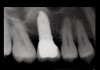

Drill depth gauge—A common complication of the crestal drill osteotomy is unintended perforation of the Schneiderian membrane. As a consequence, specific sleeves in different lengths were developed (Figure 8). These sleeves, which are placed on the drills, serve as gauge stoppers that prevent drill overextension. While the Cosci system uses only 3-mm-diameter drills, the newer systems include wider-diameter drills, which offer better visibility and control of the osteotomy and the integrity of the Schneiderian membrane. Figure 9 shows an implant insertion case using one of the newer systems to perform this crestal osteotomy technique. Osteotomy was performed with a non-cutting drill in 1-mm depth increments using depth gauge stoppers until the bone tissue is removed and the intact Schneiderian membrane is visible. The Schneiderian membrane is then elevated using bone-filling material, as described by Summers’ original technique (Figure 10). Following sufficient augmentation, the implants are inserted (Figure 11). Cone-beam computed tomography after 6 months reveals the bony mantle covering the inserted implants (Figure 12).

Fig 11. Dental implants are inserted through the crestal osteotomy preparation;

Figure 11